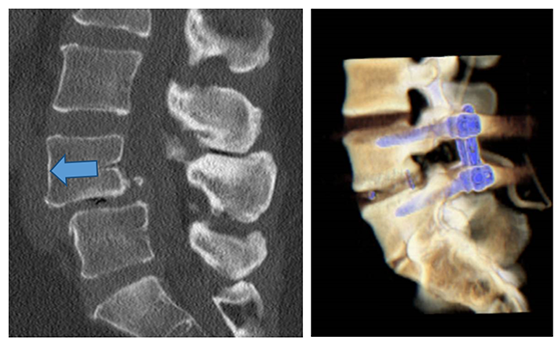

Wirbelgleiten

Abb.7: Links: Nachweis eines Wirbelgleitens zwischen dem vierten und fünften Lendenwirbelkörper. Das Abrutschen des oberen Wirbelkörpers nach vorne (Pfeil) ist Ausdruck der segmentalen Instabilität. Rechts: Diese dreidimensionale Rekonstruktion eines Operationsergebnisses zeigt die erfolgreiche Stabiliserung des vierten und fünften Lendenwirbels mittels Pedikelschrauben (blau).